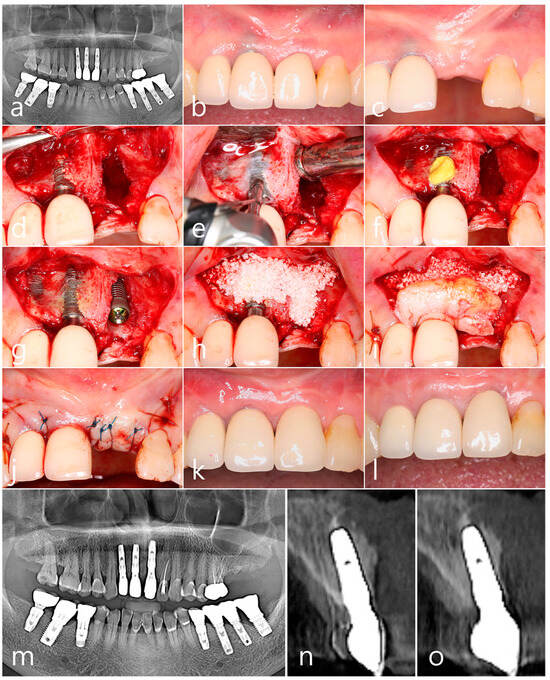

2.4. Case 4